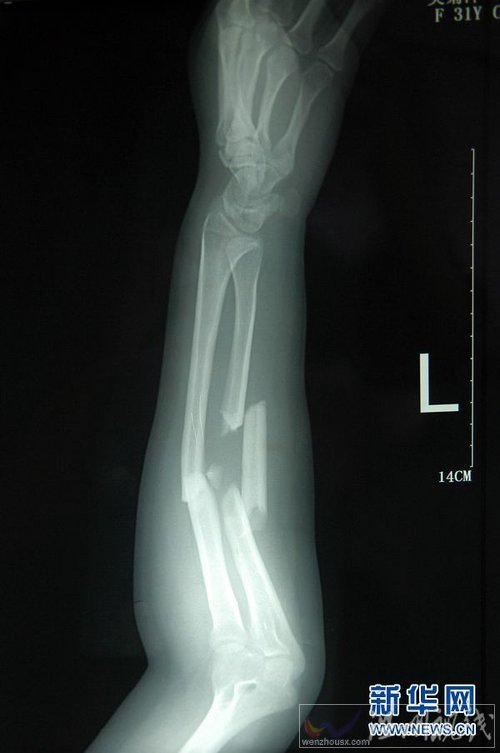

杭州英雄媽媽吳菊萍徒手接住墜樓女童 吳菊萍受傷手臂X光片

這是7月3日拍攝的吳菊萍受傷左臂的X光片,醫生診斷為手臂左尺橈骨多段粉碎性骨折。 7月2日下午1點半左右,浙江杭州濱江區的一處住宅小區內,一名2歲女童從10樓突然墜落,在樓下的吳菊萍奮不顧身地沖過去用雙手接住孩子。目前,被接住的女童正在浙江省兒童醫院搶救,而徒手接住小女孩的吳菊萍,左手臂尺橈骨多段粉碎性骨折,正在富陽市中醫骨傷醫院進行消腫處理,等待手術治療。今年31歲的吳菊萍,已有一個7個月大的兒子,一家人與墜樓女童一家同住一個小區內,事發之前素未謀面。新華社記者 黃宗治 攝